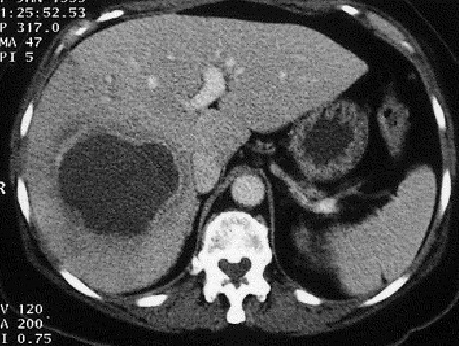

Image TDM en coupe axiale :

Aspect lesionnel une

masse a central tres hypodense et de legerement

hypodensite peripherique de sa paroi situe au lobe droit du foie .

Image radiologique peut en susgeste d'une abces

amibien |

Image radiologique TDM

d'une abces multiple encloisone du foie gauche

( coupe axiale ) |